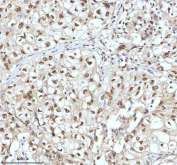

Immunohistochemical staining of IRF2BP1 using anti-IRF2BP1 antibody. IRF2BP1 was detected in a paraffin-embedded section of human clear cell renal carcinoma tissue. Heat mediated antigen retrieval was performed in EDTA buffer (pH 8.0, epitope retrieval solution). The tissue section was blocked with 10% goat serum. The tissue section was then incubated with 2 ug/ml rabbit anti-IRF2BP1 antibody overnight at 4oC. Peroxidase Conjugated Goat Anti-rabbit IgG was used as secondary antibody and incubated for 30 minutes at 37oC. The tissue section was developed using an HRP secondary and DAB substrate.